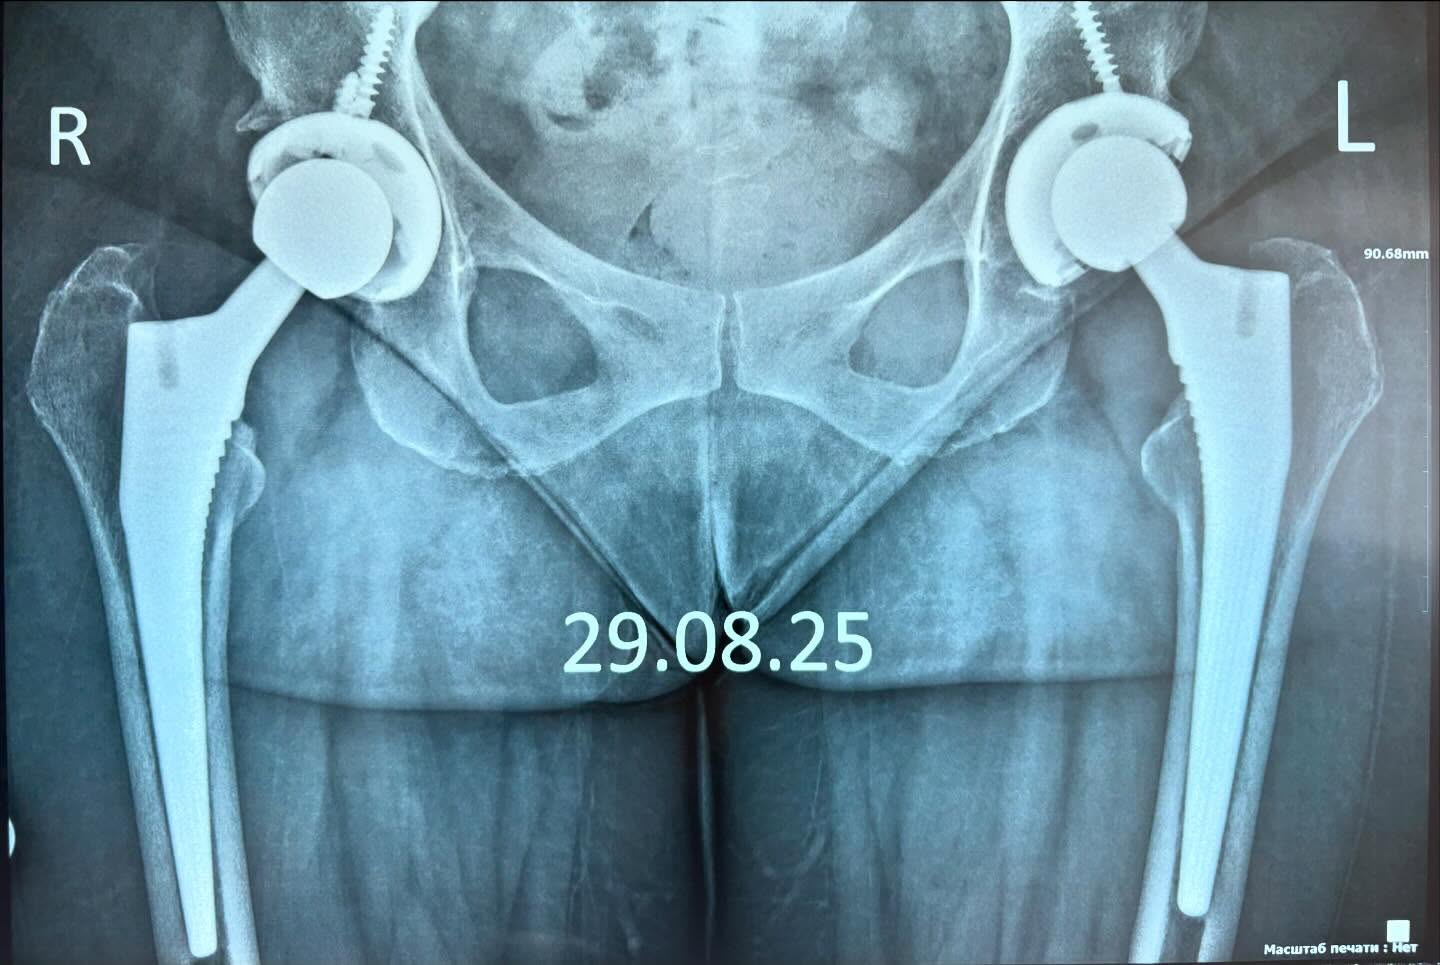

Полная замена тазобедренного сустава

На фото видим удачный пример полной замены (двустороннего эндопротезирования) тазобедренного сустава.Что сказать – если через 2 месяца после операции пациент приходит на приём, при этом не имеет жалоб и на вопрос о целях посещения и беспокоит ли что-то, отвечает – всё хорошо, вы сами сказали прийти через 2 месяца на осмотр, значит работа выполнена 100% так, как нужно.И это очень приятно.